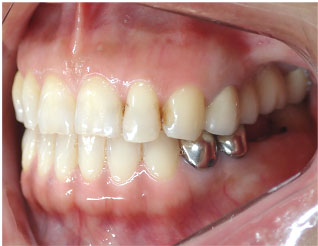

- ブリッジ 症例写真 B-0113FZC8本 女性モニターの方です。

この方は古い差し歯の黄ばみを治したいとご来院されました。 奥歯に欠損もありましたので、前歯はジルコニアセラミック、奥はジルコニアブリッジで治しました。 1回の治療で前歯も奥歯も同時進行で治療します。 1回目の治療時に仮歯を入れますので、すぐに見た目が気にならなくなります。 治療回数は5回でした。